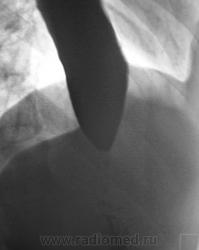

"Картинка" через 1 час после приема водной взвеси сернокислого бария.

классика ахалазии кардии, 3 ст. симптом  "мышинного хвоста".

Ахалазия кардии.

+